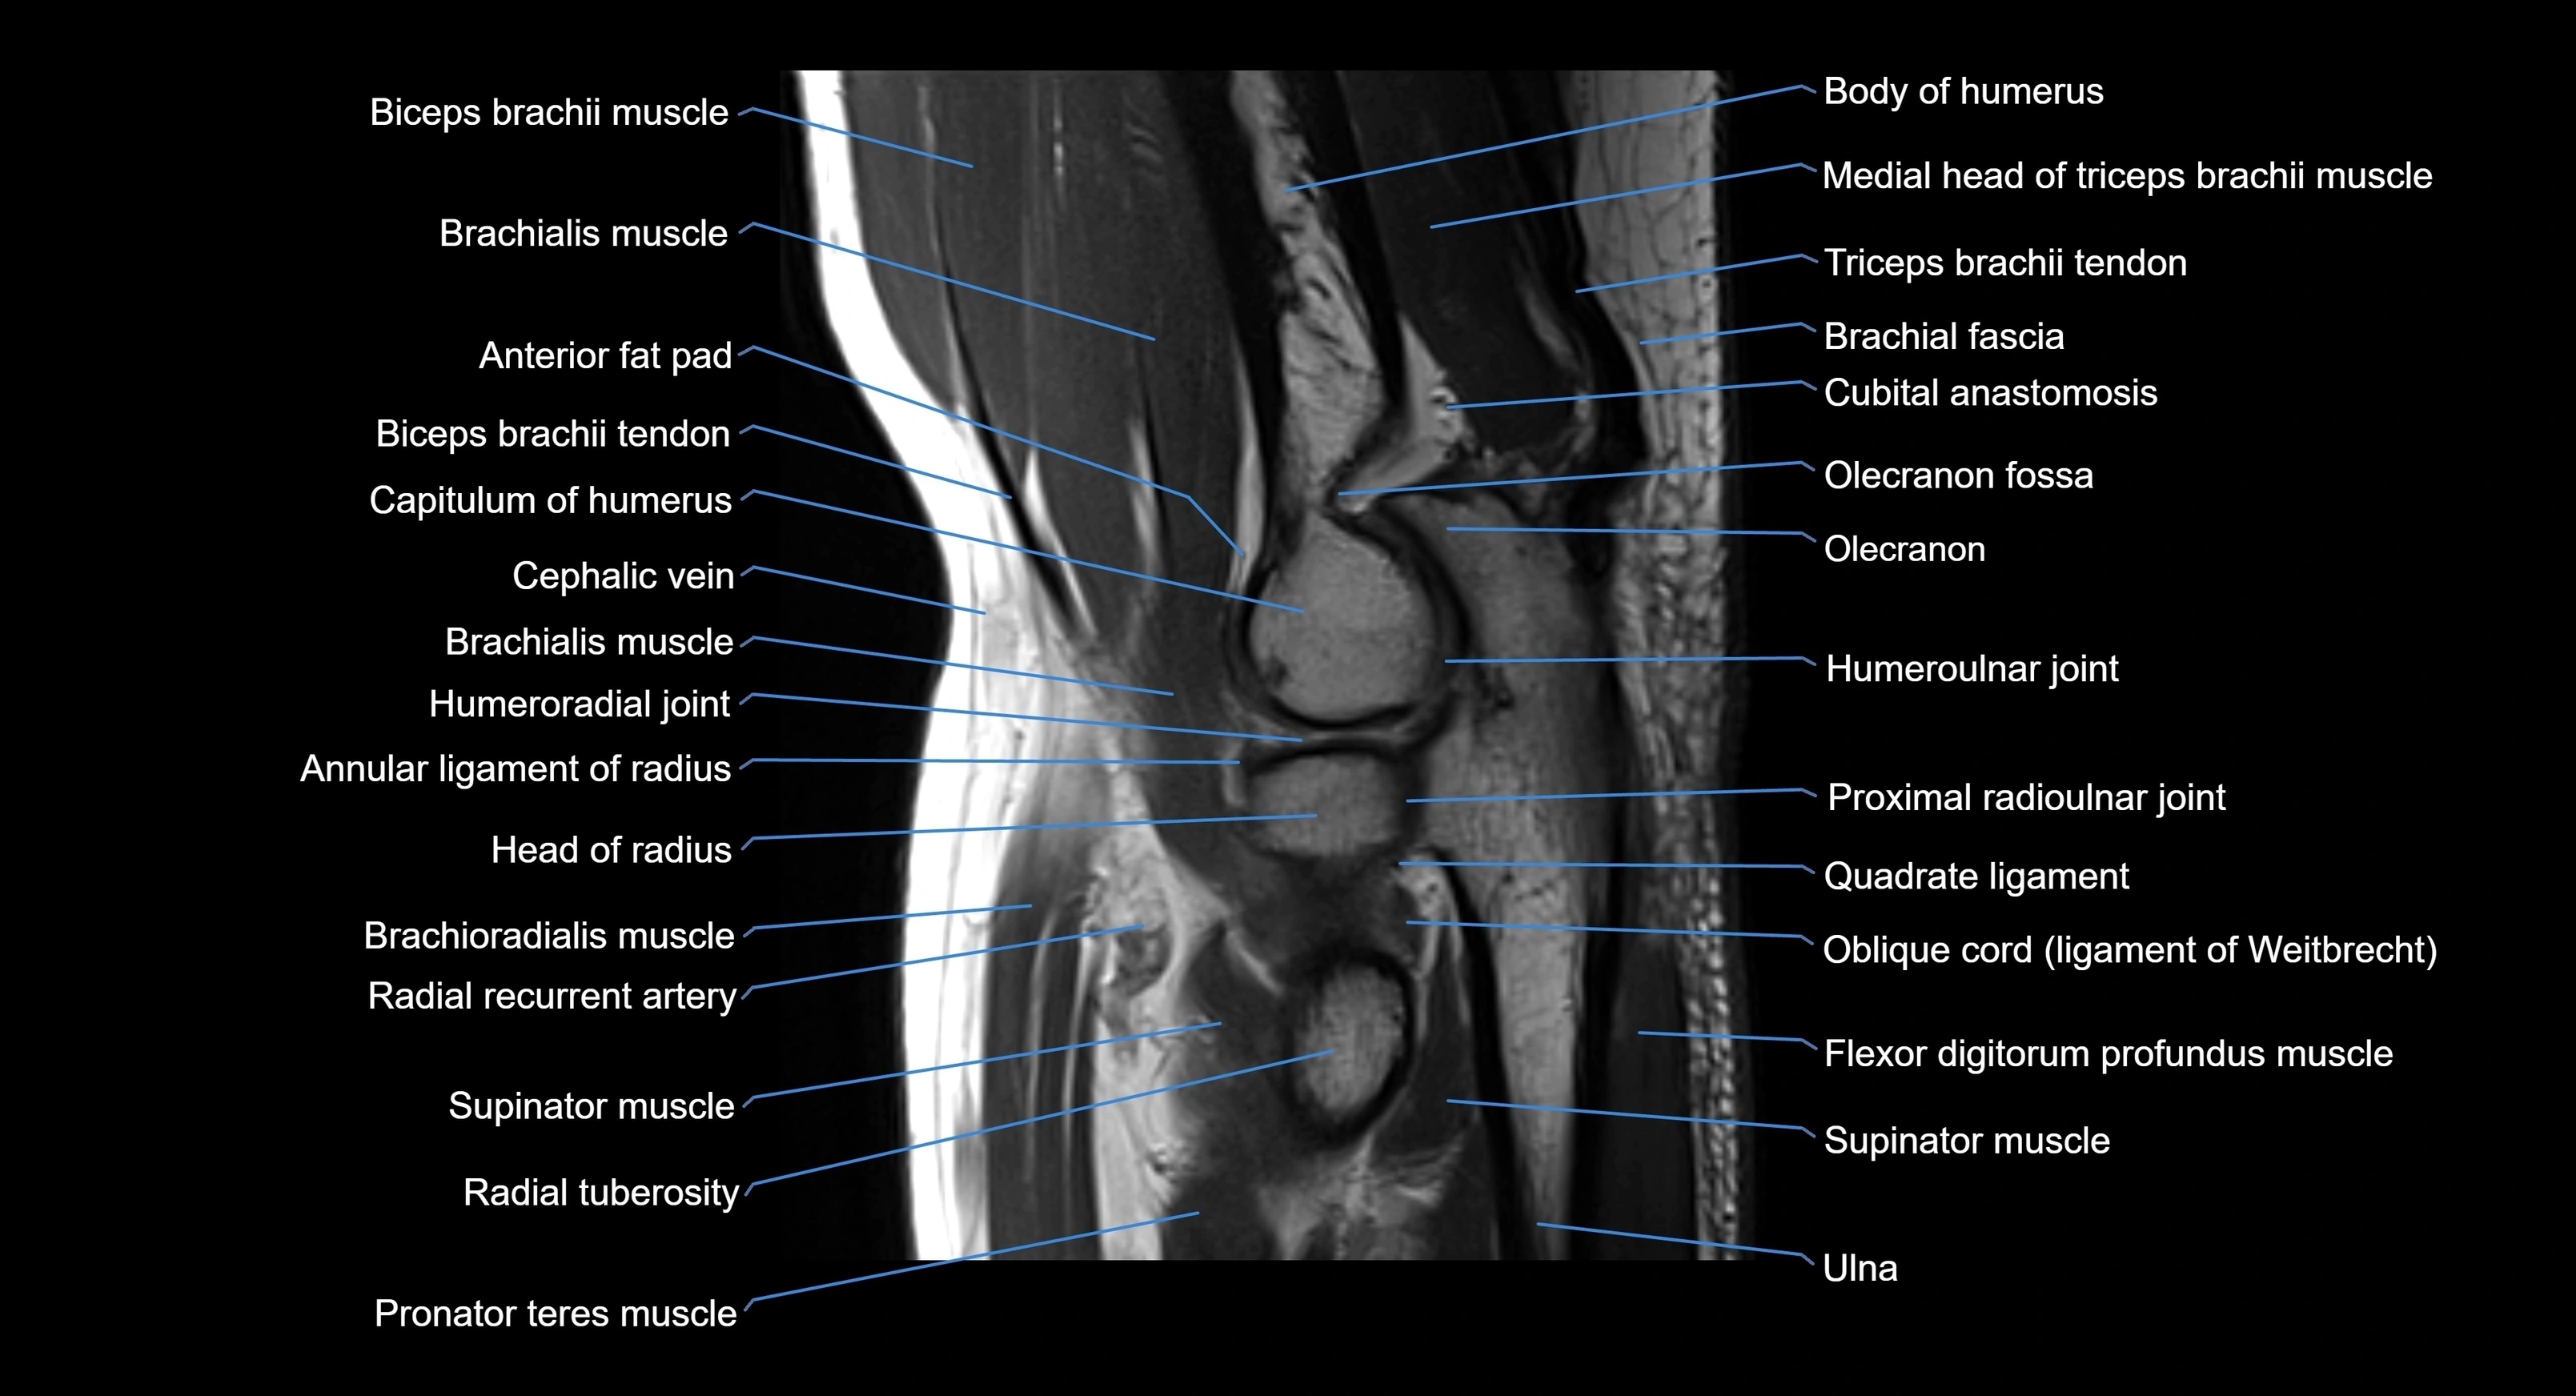

MRI image

image